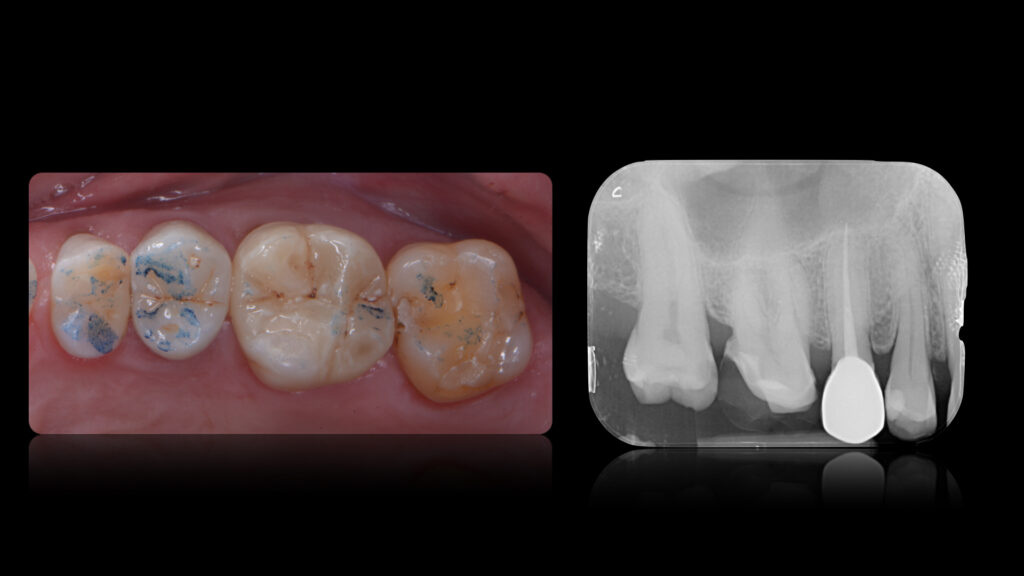

Paziente di 55 anni, presenta il 1° quadrante con gravi problematiche restaurative/endodontiche in particolare processi cariosi multipli ai danni degli elementi 1.4 - 1.5 - 1.6 - 1.7.

L’elemento 1.5 presenta altresì una compromissione dell’integrità del sigillo endodontico, ragione per la quale si è optato per il ritrattamento dell’elemento con contestuale cementazione di due perni in fibra di vetro.